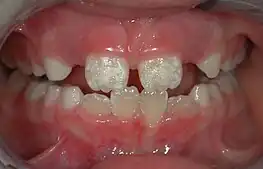

The normal color of enamel varies from light yellow to grayish (bluish) white. It has been suggested that the color is determined by differences in the translucency of enamel, yellowish teeth having a thin, translucent enamel through which the yellow color of the dentin is visible and grayish teeth having a more opaque enamel. The translucency may be attributable to variations in the degree of calcification and homogeneity of the enamel. At the edges of teeth where there is no dentin underlying the enamel, the color sometimes has a slightly blue or translucent off-white tone, easily observable on the upper incisors. Since enamel is semitranslucent, the color of dentin and any material underneath the enamel strongly affects the appearance of a tooth. The enamel on primary teeth has a more opaque crystalline form and thus appears whiter than on permanent teeth.

Some groups have spoken out against fluoridated drinking water, for reasons such as the neurotoxicity of fluoride or the damage fluoride can do as fluorosis. Fluorosis is a condition resulting from the overexposure to fluoride, especially between the ages of 6 months and 5 years, and appears as mottled enamel.[3] Consequently, the teeth look unsightly, although the incidence of dental decay in those teeth is very small. Where fluoride is found naturally in high concentrations, filters are often used to decrease the amount of fluoride in water. For this reason, codes have been developed by dental professionals to limit the amount of fluoride a person should take.[36] These codes are supported by the American Dental Association and the American Academy of Pediatric Dentistry.

There are 14 different types of amelogenesis imperfecta.[3] The hypocalcification type, which is the most common, is an autosomal dominant condition that results in enamel that is not completely mineralized.[51] Consequently, enamel easily flakes off the teeth, which appear yellow because of the revealed dentin. The hypoplastic type is X-linked and results in normal enamel that appears in too little quantity, having the same effect as the most common type.[51]

Enamel hypoplasia is broadly defined to encompass all deviations from normal enamel in its various degrees of absence.[53] The missing enamel could be localized, forming a small pit, or it could be completely absent.